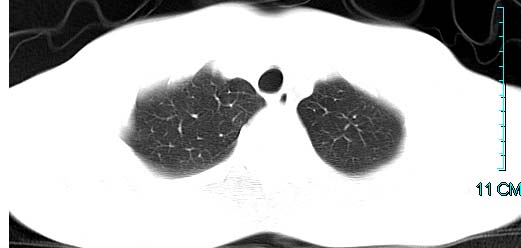

以下是引用ctkz987在2006-3-28 13:04:00的发言:[br]左侧胸腔积液穿刺后多发气液平(多房性),结合临床有高热不除外合并感染。

以下是引用qian在2006-3-28 14:32:00的发言:[br]左肺下叶大片状阴影,密度不均,见有条片影和空洞及气液平,少量胸腔积液伴有胸膜增厚,从图像看积液密度比水的密度高,结合病史,考虑左下肺化脓性炎症伴有脓胸。

以下是引用wawaquan在2006-3-28 22:25:00的发言:[br]左上肺舌段多发斑片影。结合“男24y咳嗽咳痰气促伴高热(38.5--39.5)20多天”及穿刺史,[br]考虑1 左下肺化脓性炎症;2脓胸。

以下是引用乡医在2006-3-28 18:37:00的发言:[br]左侧多发液气平面结合患者男24y咳嗽咳痰气促伴高热(38.5--39.5)20多天,查胸水:ldh239.3,总蛋白59.19,tb-ab阴性,利凡它试验+,红c2.7*109,白c1.08*109,分类淋巴92%分叶8%,考虑1脓胸2肺隔离征感染